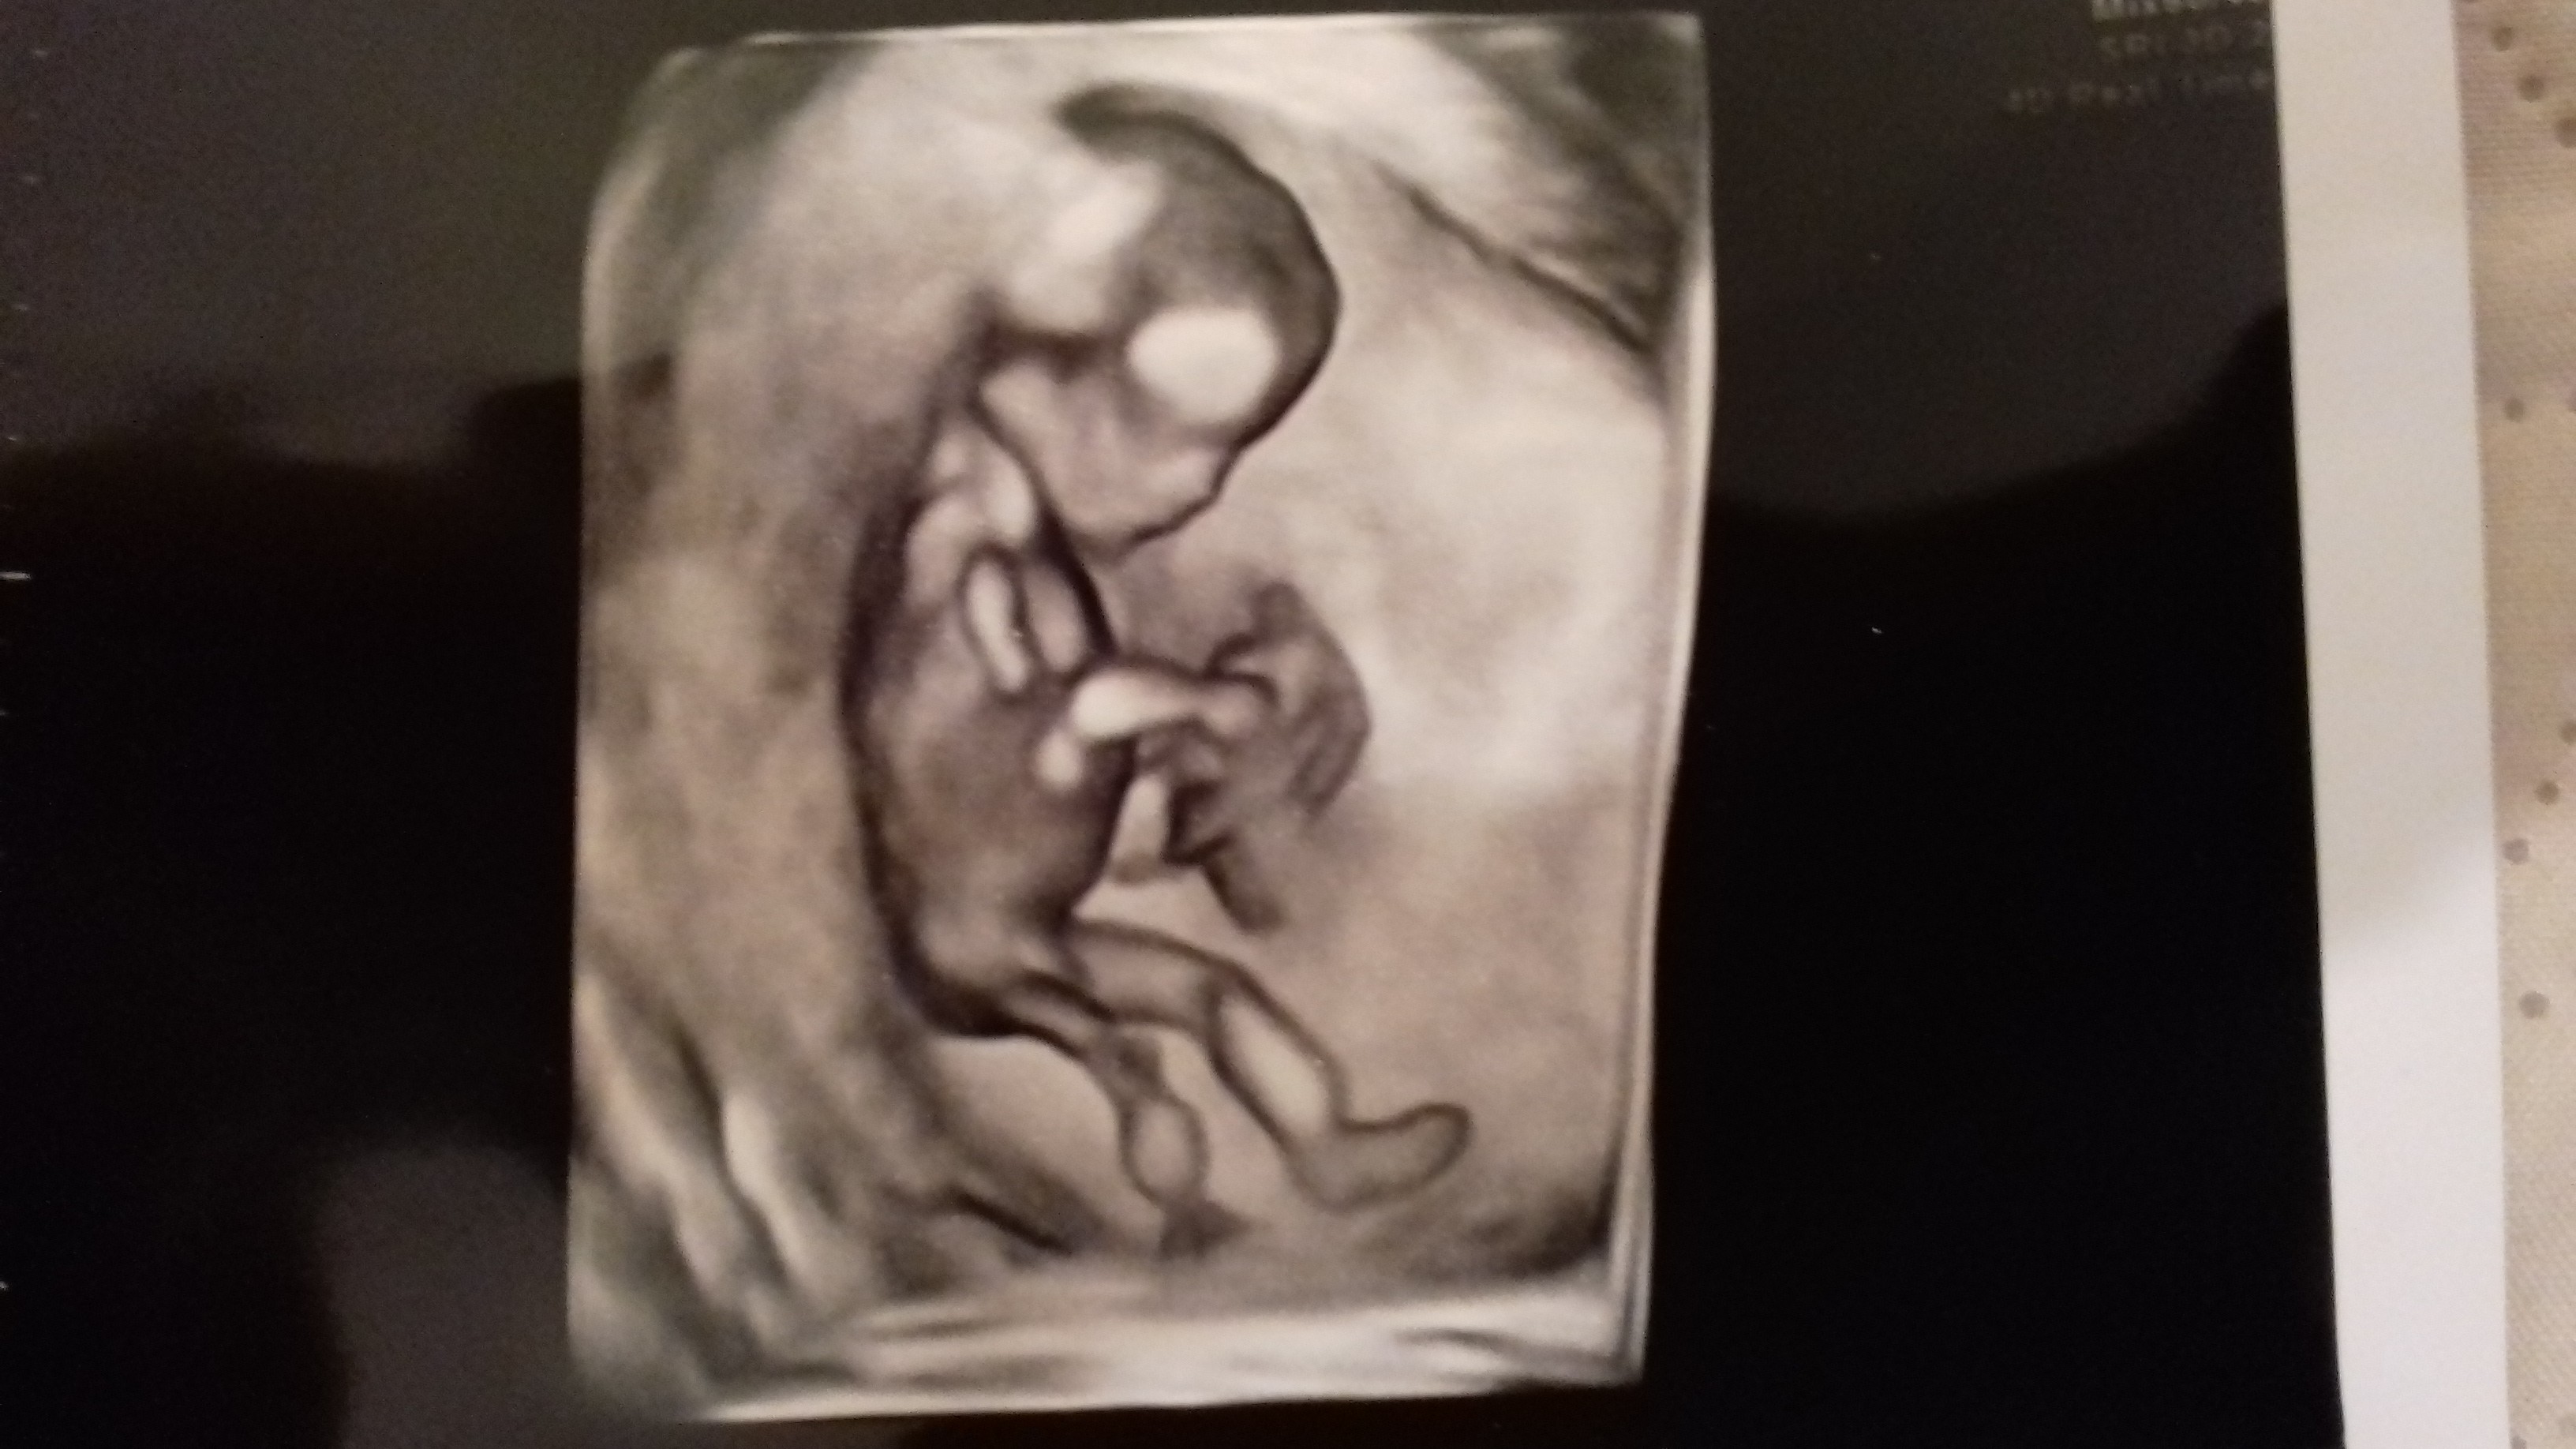

Pochwalę się i tuZobacz załącznik 895748

Czy ja dobrze widzę chłopaczka?

Śliczne zdjęcie! A ktory to tc? W tych początkowych tygidniach wszystkie dzieci wyglądają jak chłopaczki [emoji14]Ja też widzę chłopaczka. Lekarz nie chciał potwierdzić ale każdy, kto spojrzy na zdjecie widzi ptaszka.![]()

Śliczne zdjęcie! A ktory to tc? W tych początkowych tygidniach wszystkie dzieci wyglądają jak chłopaczki [emoji14]

U mnie na prenatalnych dałabym sobie reke uciac, ze sidzialam siurka poniedzy nogami, a.lekarz.mi na to, ze raczej dziewczynka. Ja mowie ale jak dziewczynak, jak.cos odstaje [emoji14] lekarz na to, ze to wyrostek.plciowy, ktory w tych tygidniach wyglada jak siurek, tylko on po kącie nachylenia jest w stanie określic czy to dziewczynka, czy chłopiec. I faktycznie miesiac pozniej juz nic nie odstawało i jest dziewczynka [emoji14] Dlatego bardzo wielu lekarzy na pierwszych prenatalnych nie chce mowic o płci [emoji14]13. A to ciekawe, rzeczywiście wygląda podobnie.

U mnie na prenatalnych dałabym sobie reke uciac, ze sidzialam siurka poniedzy nogami, a.lekarz.mi na to, ze raczej dziewczynka. Ja mowie ale jak dziewczynak, jak.cos odstajelekarz na to, ze to wyrostek.plciowy, ktory w tych tygidniach wyglada jak siurek, tylko on po kącie nachylenia jest w stanie określic czy to dziewczynka, czy chłopiec. I faktycznie miesiac pozniej juz nic nie odstawało i jest dziewczynka

Czekanie jest ciezkie [emoji14] ja niby mowiłam, ze wszystko jedno jaka płec, ale z drugiej strony nie mogłam sie doczekac, żeby już wiedzieć hahaNo właśnie, teraz widzę, że to wygwyglądało jak ten wyrostek płciowy na zdjęciach. Więc sprawa jest nadal otwarta.![]()